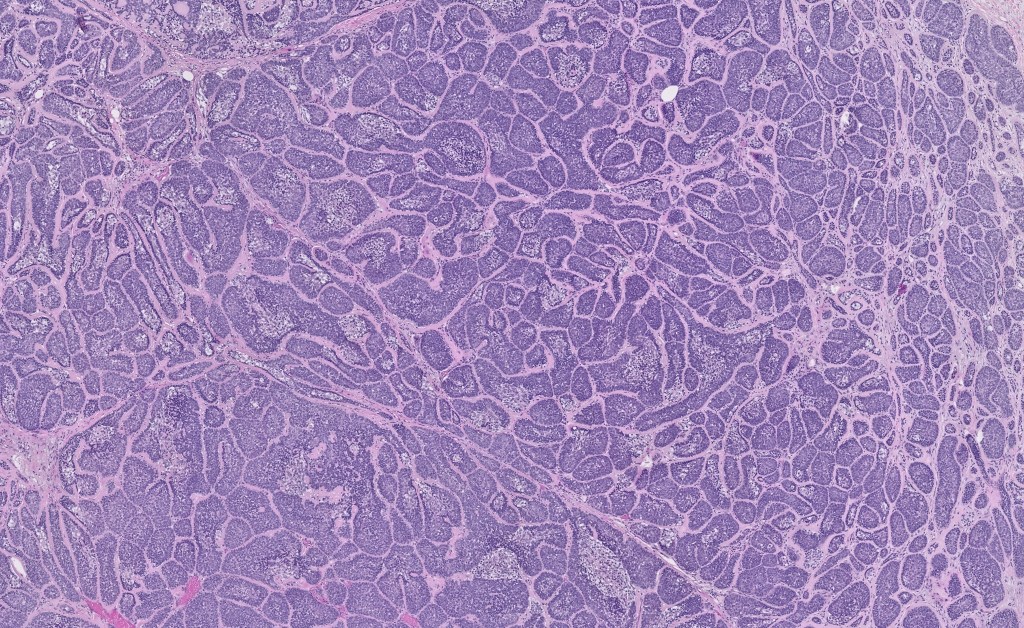

Histological features

•Dermal based

•Jigsaw/mosaic pattern arrangement of variably sized lobules of tumor cells with surrounding think, eosinophilic hyaline basement membrane

•Intralobular hyaline basement membrane material droplets

•Outer layer of intensely basophilic small cells surrounding larger central cells with pale staining or eosinophilic cytoplasm & vesicular nuclei

•Spiradenocylindroma